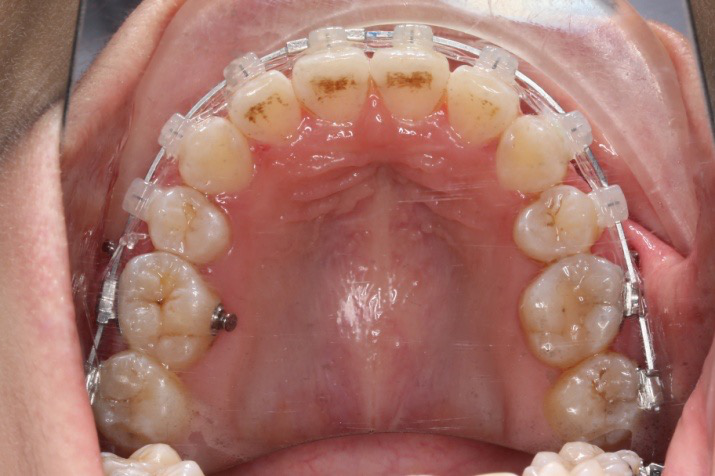

牙根基本平行,未见牙根吸收

10 M after Post-Tx

10 M after Post-Tr

2019.08.06  术后  10个月复查